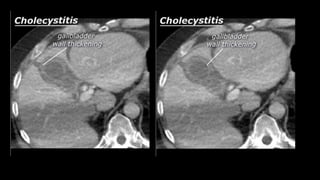

• Cholecystitis

• A complication of bile stones is an infected

gallbladder or cholecystitis. Cholecystitis

rarely occurs in the absence of bile stones.

Ultrasound is also best suited to diagnose

cholecystitis. Ultrasound improves the

visibility of the bile stones, and gallbladder

compressibility can be evaluated (dynamic

examination). Absent compressibility

constitutes a key characteristic of

cholecystitis (see abdominal ultrasound

class). Other characteristics of cholecystitis

on CT include gallbladder wall thickening

and infiltration of the fat surrounding the

gallbladder. A common complication of

cholecystitis is gallbladder perforation,

where bile leaks into the abdominal cavity

(biloma).

• Cholecystitis • Acomplication of bile stones is an infected gallbladder or cholecystitis. Cholecystitis rarely occurs in the absence of bile stones. Ultrasound is also best suited to diagnose cholecystitis. Ultrasound improves the visibility of the bile stones, and gallbladder compressibility can be evaluated (dynamic examination). Absent compressibility constitutes a key characteristic of cholecystitis (see abdominal ultrasound class). Other characteristics of cholecystitis on CT include gallbladder wall thickening and infiltration of the fat surrounding the gallbladder. A common complication of cholecystitis is gallbladder perforation, where bile leaks into the abdominal cavity (biloma).